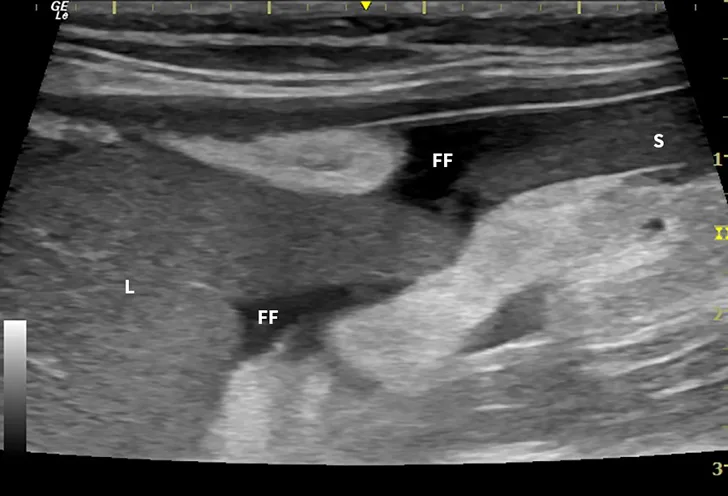

Abdominal ultrasound images from a cat.

FIGURE 1

Ultrasound image showing abdominal effusion in a cat with wet FIP. Anechoic fluid is present between organs, distending the abdomen. FF = free fluid; L = liver; S = spleen; K = kidney